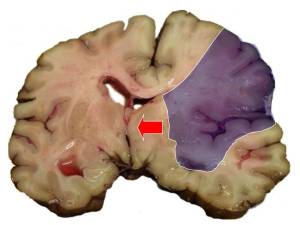

Sağlamlıq Sağlamlıq İnsult – beyin qan dövranının kəskin pozulması nəticəsində baş beyində ocaqlı zədələnmənin yaranması ilə xarakterizə olunur. İşemik və ya hemorragik x Laura's 1 28.10.2024